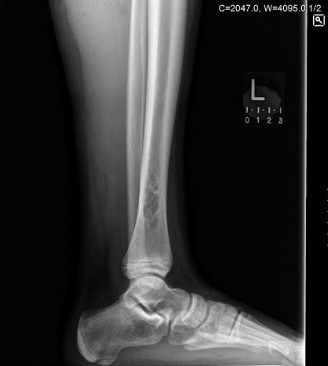

A 16-year-old female sprains her ankle playing lacrosse and is brought to the emergency room. X-rays are nega…